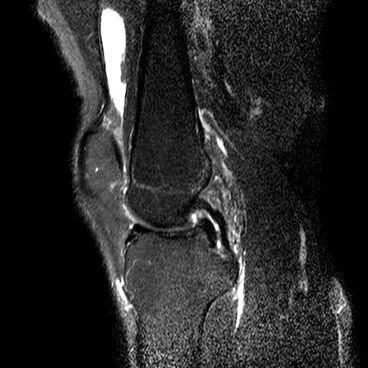

1、水平撕裂

2、较少见3、III级高信号与胫骨平台平行,到达半月板的游离缘或一侧关节面

(半月板水平撕裂)